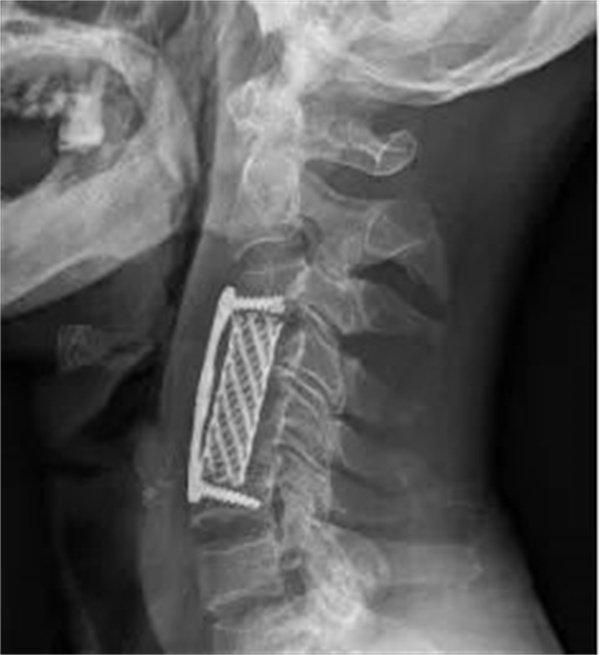

患者完善术前准备后,手术由刘辉主任医师主刀、熊志鹏副主任协助。术中全麻后颈椎脱位经手法复位完全纠正,前路椎体次全切除后脊髓减压充分,融合器及内固定装置植入标准,颈椎稳定性恢复可靠。手术用时仅1小时,出血仅50毫升,组织损伤小,手术顺利完成!

术后